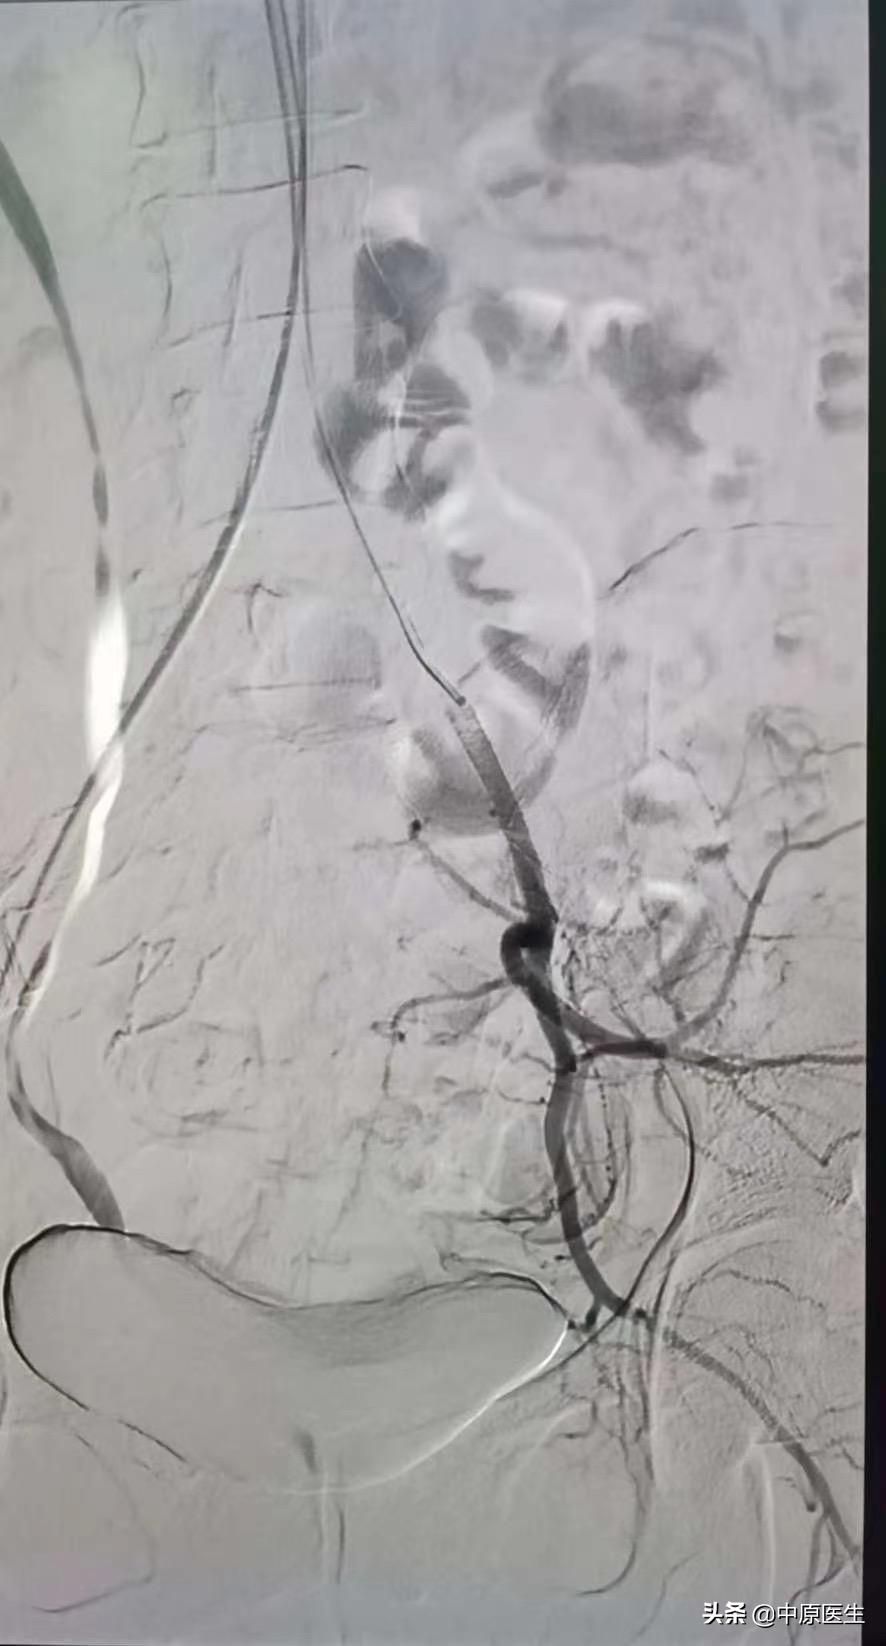

治疗计划制定后,我们立刻行动马,谁知一做血管造影才发现,怪哉!此女子非凡人也!两侧子宫动脉均不同于一般人,一侧是由卵巢动脉(锯齿状血管)长途奔袭去供应子宫血液,一侧是从阴部内动脉发出,两个血管发出角度都很刁钻,血管走形迂曲又比较细,做这样的血管介入类似于医学版“爬雪山过草地”,大家不禁倒吸了一口冷气!

难题摆在这,再难的骨头也得啃,再难的血管也得搞啊!谁让我们是医生呢!谁让患者的血管都不像教科书长得那样标准呢!跟自己鼓足劲,打打气,刘建文主任再次出发,见招拆招,小心翼翼,利用导管、导丝巧妙配合,更是他的耐心、细心、信心及过硬介入操作技术,战胜了种种不利因素,经过两个多小时的艰苦奋战,在有害射线的辐射下,浑身的衣服都湿透了,最后终于成功将两侧血管完美栓塞!利用自己的微创介入医学技术为妇产科医生手术保驾护航,为手术创造了安全的条件,终于保住了患者的子宫!尽管这样的手术太苦太累,当看到最后的手术图片,刘主任又露出了一贯的笑容,还不忘在综合介入微信群里跟大家做了一下交流和总结!